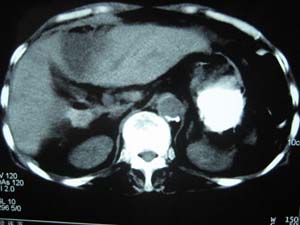

标题: CT15625:女性78Y,十天前胃镜示胃穿孔,现低热 [打印本页]

标题: CT15625:女性78Y,十天前胃镜示胃穿孔,现低热

肝脓肿/膈下脓肿?

膈下脓肿

隔下肿脓.

支持--膈下脓肿

膈下及肝脓肿。

考虑多发性肝脓肿。